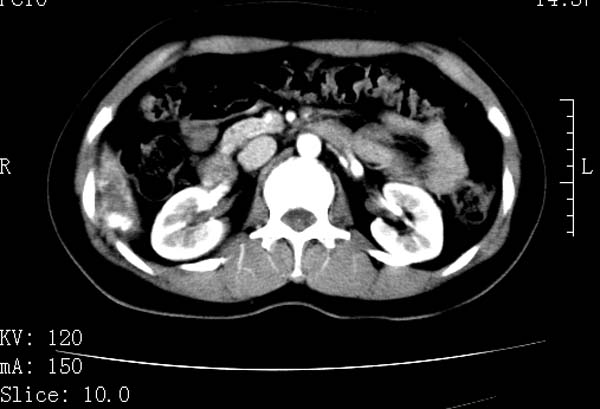

标题: CT22086:女44岁 肝右叶占位增强示巨大血管瘤,门脉期发现小 [打印本页]

标题: CT22086:女44岁 肝右叶占位增强示巨大血管瘤,门脉期发现小

请大家观察一下小灶   发表意见,谢谢

小病灶也是血管瘤。

支持肝右叶血管瘤诊断。小灶是否为囊肿,

肝右叶海绵状血管瘤,小灶也是血管瘤。

肝海绵状血管瘤ct平扫常呈均匀低密度,与邻近血管密度相仿。在脂肪肝背景下可呈相对高密度。在增强扫描时,一般早期(动脉期)呈周边结节状或弧形强化,其密度与同层面的血管密度相仿,随着时间延迟向中央渐进性充填,注药后5~7分钟,逐渐扩大至全瘤强化,强化密度逐渐降至稍高于或等于正常肝脏。大的血管瘤往往中央有星形、大的低密度区,可以为纤维化或囊性变所致,纤维化成分可在延迟2 o分钟时完全充填,呈等密度,但囊变区则不会强化。不典型ct表现常见于≤3 cm的小血管瘤。小的血管瘤可以在动脉期即呈全部致密的均匀强化,不呈典型的周边结节状强化表现,但其密度往往较高,与主动脉相仿,在延迟期呈高或等密度。其他不典型的ct表现有:增强扫描强化不明显,呈点状较轻程度的强化,充填慢,可能与供血动脉较细和较大的血管间隙有关以及中央先强化等。

延迟扫描三个病灶都呈等密度改变。肝多发血管瘤,较典型。